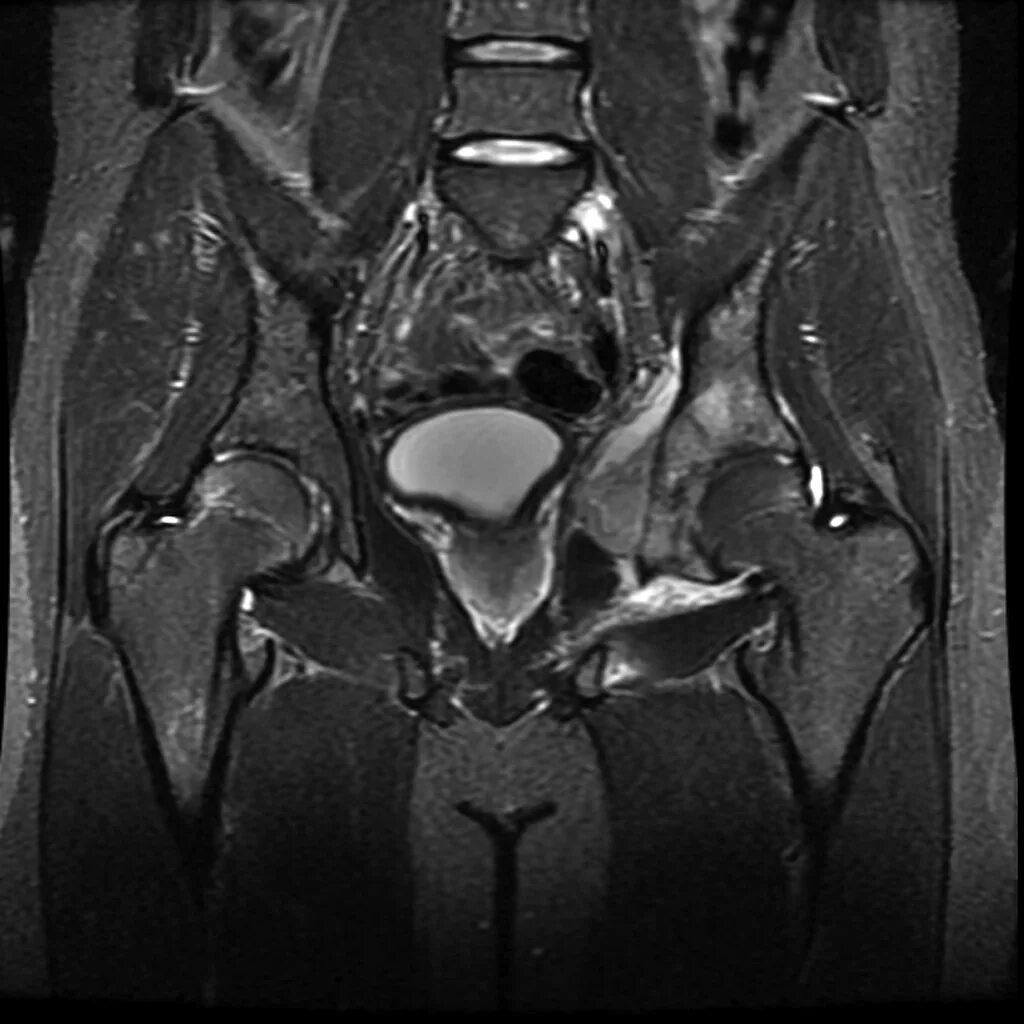

Саркома мрт